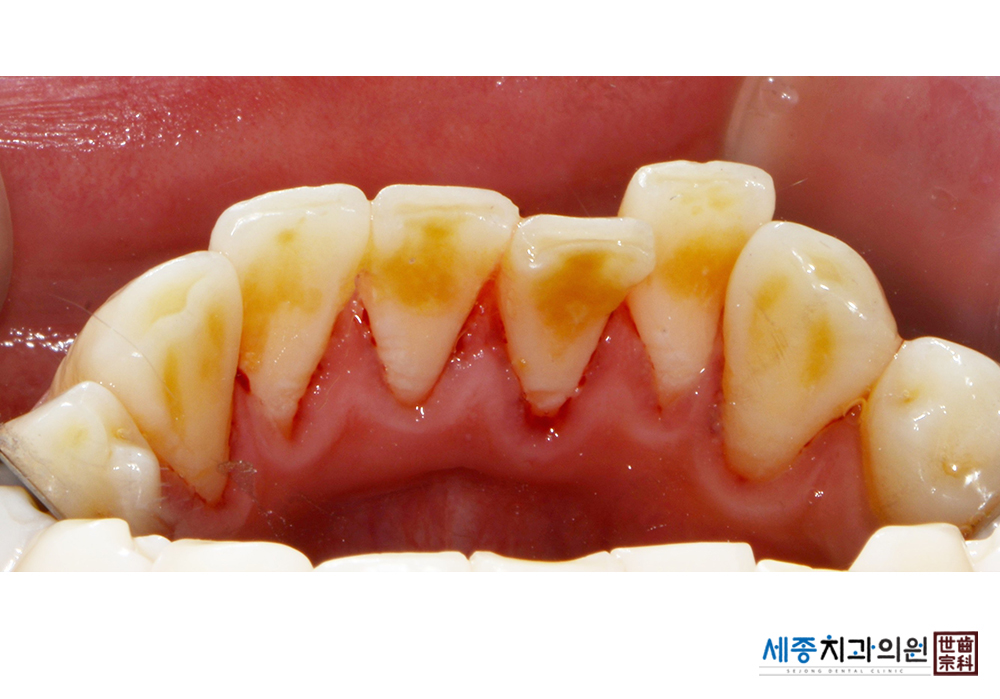

[스케일링] 치주질환 예방 스케일링

치료전 : 2021-01-07

치료후 : 2021-01-07

가글마취&저주파 스켈러를 사용한 스케일링